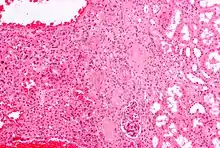

| Micrograph of a renal oncocytoma. |

A renal oncocytoma is a tumour of the kidney made up of oncocytes, epithelial cells with an excess amount of mitochondria.[1][2]

Renal oncocytoma is thought to arise from the intercalated cells of collecting ducts of the kidney. It represent 5% to 15% of surgically resected renal neoplasms. Ultrastructurally, the eosinophilic cells have numerous mitochondria.

Histologic appearance

An oncocytoma is an epithelial tumor composed of oncocytes, large eosinophilic cells having small, round, benign-appearing nuclei with large nucleoli and excessive amounts of mitochondria.

In gross appearance, the tumors are tan or mahogany brown, well circumscribed and contain a central scar. They may achieve a large size (up to 12 cm in diameter).

The main differential diagnosis of renal oncocytoma is chromophobe renal cell carcinoma oncocytic variant, which like the renal oncocytoma has eosinophilic cytoplasm, but has perinuclear clearing and, typically, some degree of nuclear atypia.